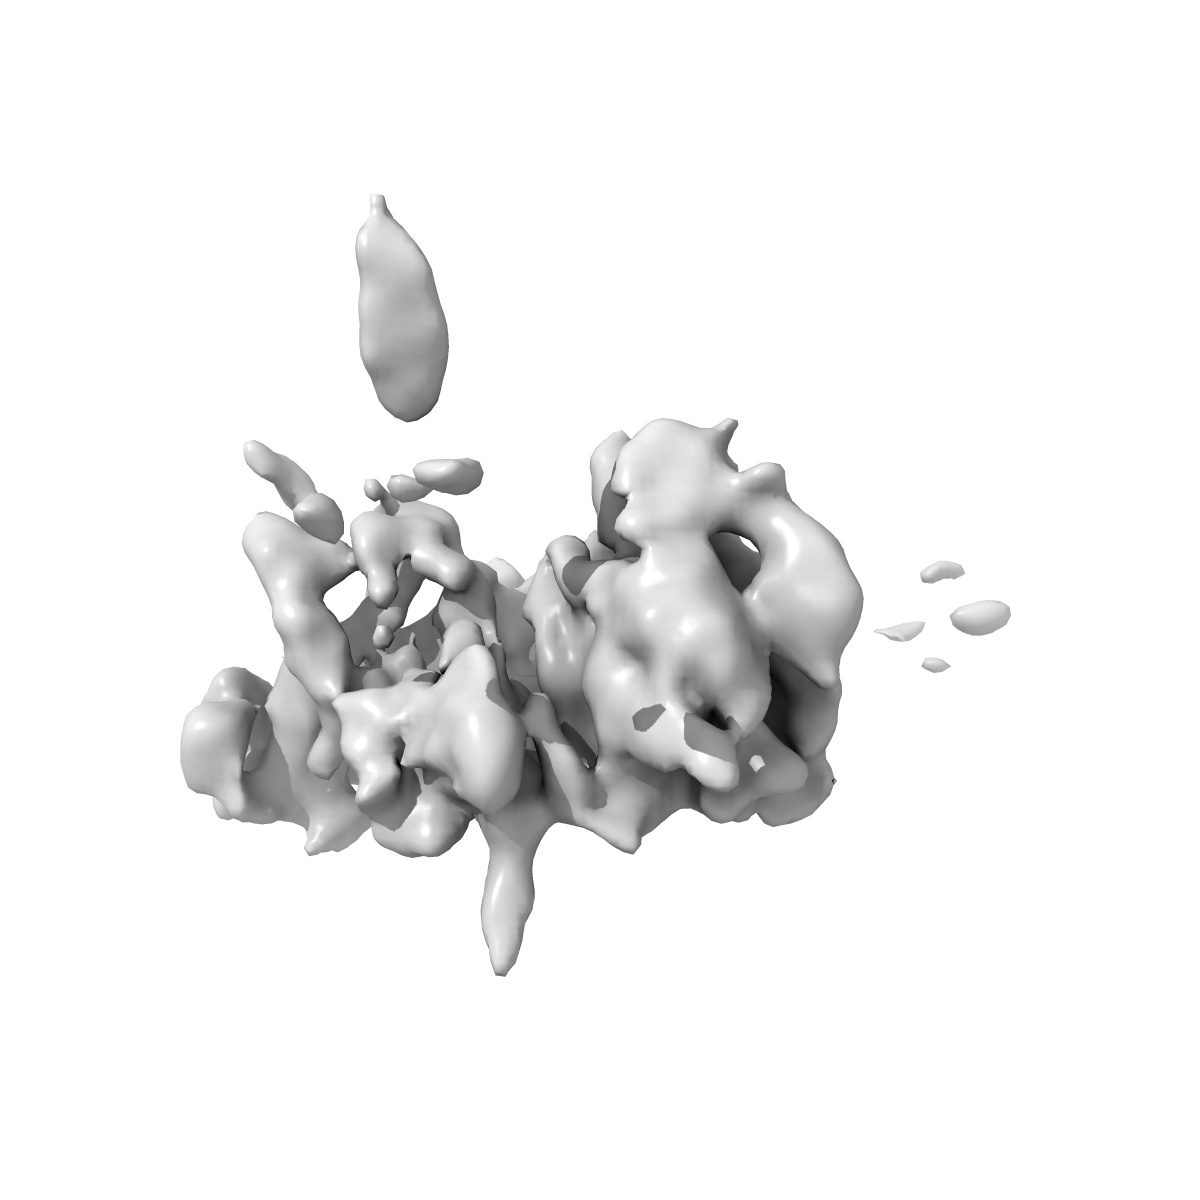

Rapid screening cryo-EM map of CAK bound to ICEC0768 (grid VC2-1, 1hr collection)

Single-particle4.3 Å

Sample: CDK-activating kinase

High-resolution cryo-EM of the human CDK-activating kinase for structure-based drug design.

(2024) Nat Commun , 15 , 2265 - 2265